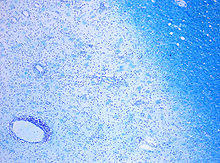

CD68-stained tissue shows several macrophages in the area of a demyelinated lesion caused by MS. | |